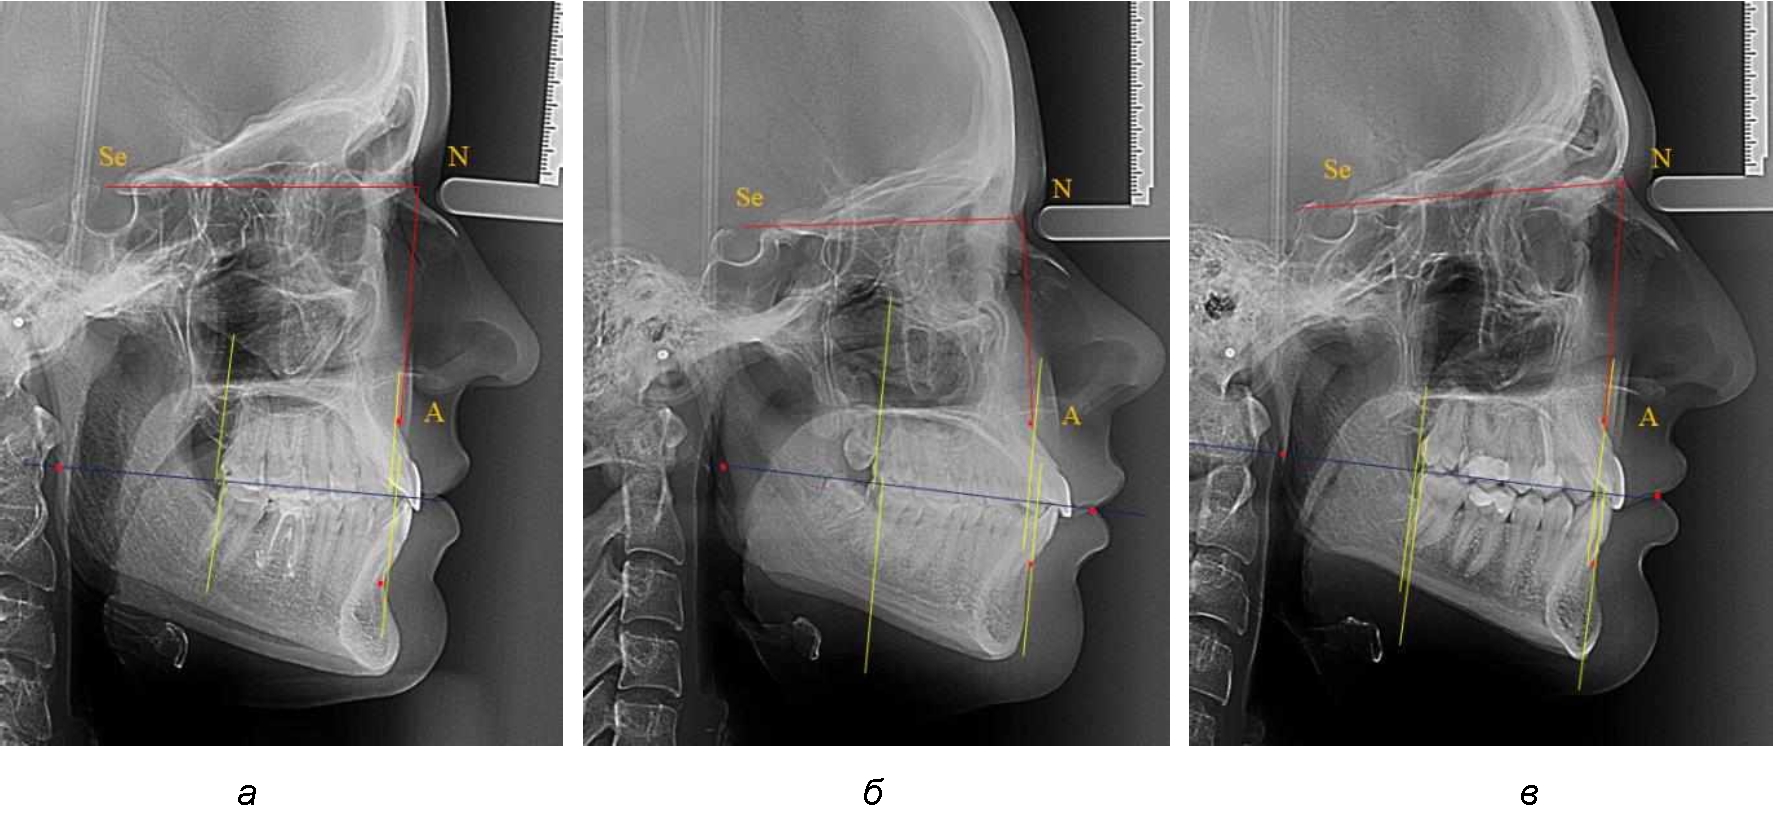

Расстояние от конструируемой точки окклюзионной плоскости на ветви челюсти («rmРOcP») до апикальных точек Downs на обеих челюстях также коррелировало между собой, и средняя величина различия показателей составляла (1,23 ± 0,69) мм. Проекция нижней апикальной точки на окклюзионную линию, как правило, располагалась несколько кпереди проекции верхней апикальной точки, на величину около 1 мм, что соответствовало оптимальным данным Wits-анализа.

Аналогичное расстояние было отмечено и при расположении дистальных окклюзионных точек верхней и нижней челюсти (рис. 2).

Рис. 2. Положение апикальных точек и челюстей при нормопозиции (а), антепозиции (б) и ретропозиции (в) верхней челюсти